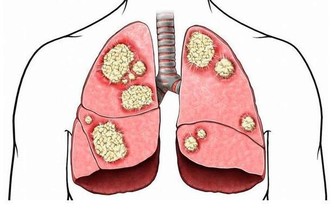

2、如果伴有其他症狀,請諮詢醫生看看

發燒、嘔吐、噁心、發暈、左臂疼痛或者胸部疼痛、下巴難以夠到胸部。